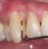

Poza PARODONTOLOGIE

1. PARODONTOLOGIE

Parodontologia este o ramură a stomatol ..